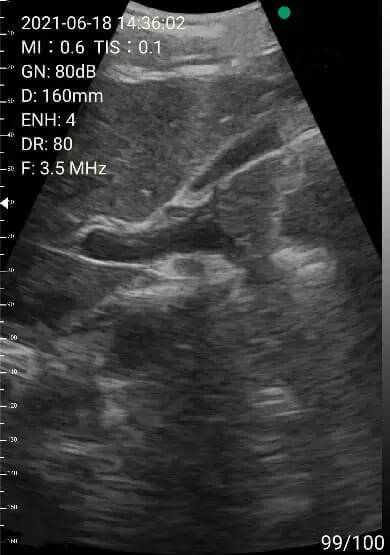

2. Abdomen review

Left lobe of liver

Portal area

Right lobe of liver

Images of thyoid scan on a 35-year-old healthy man.